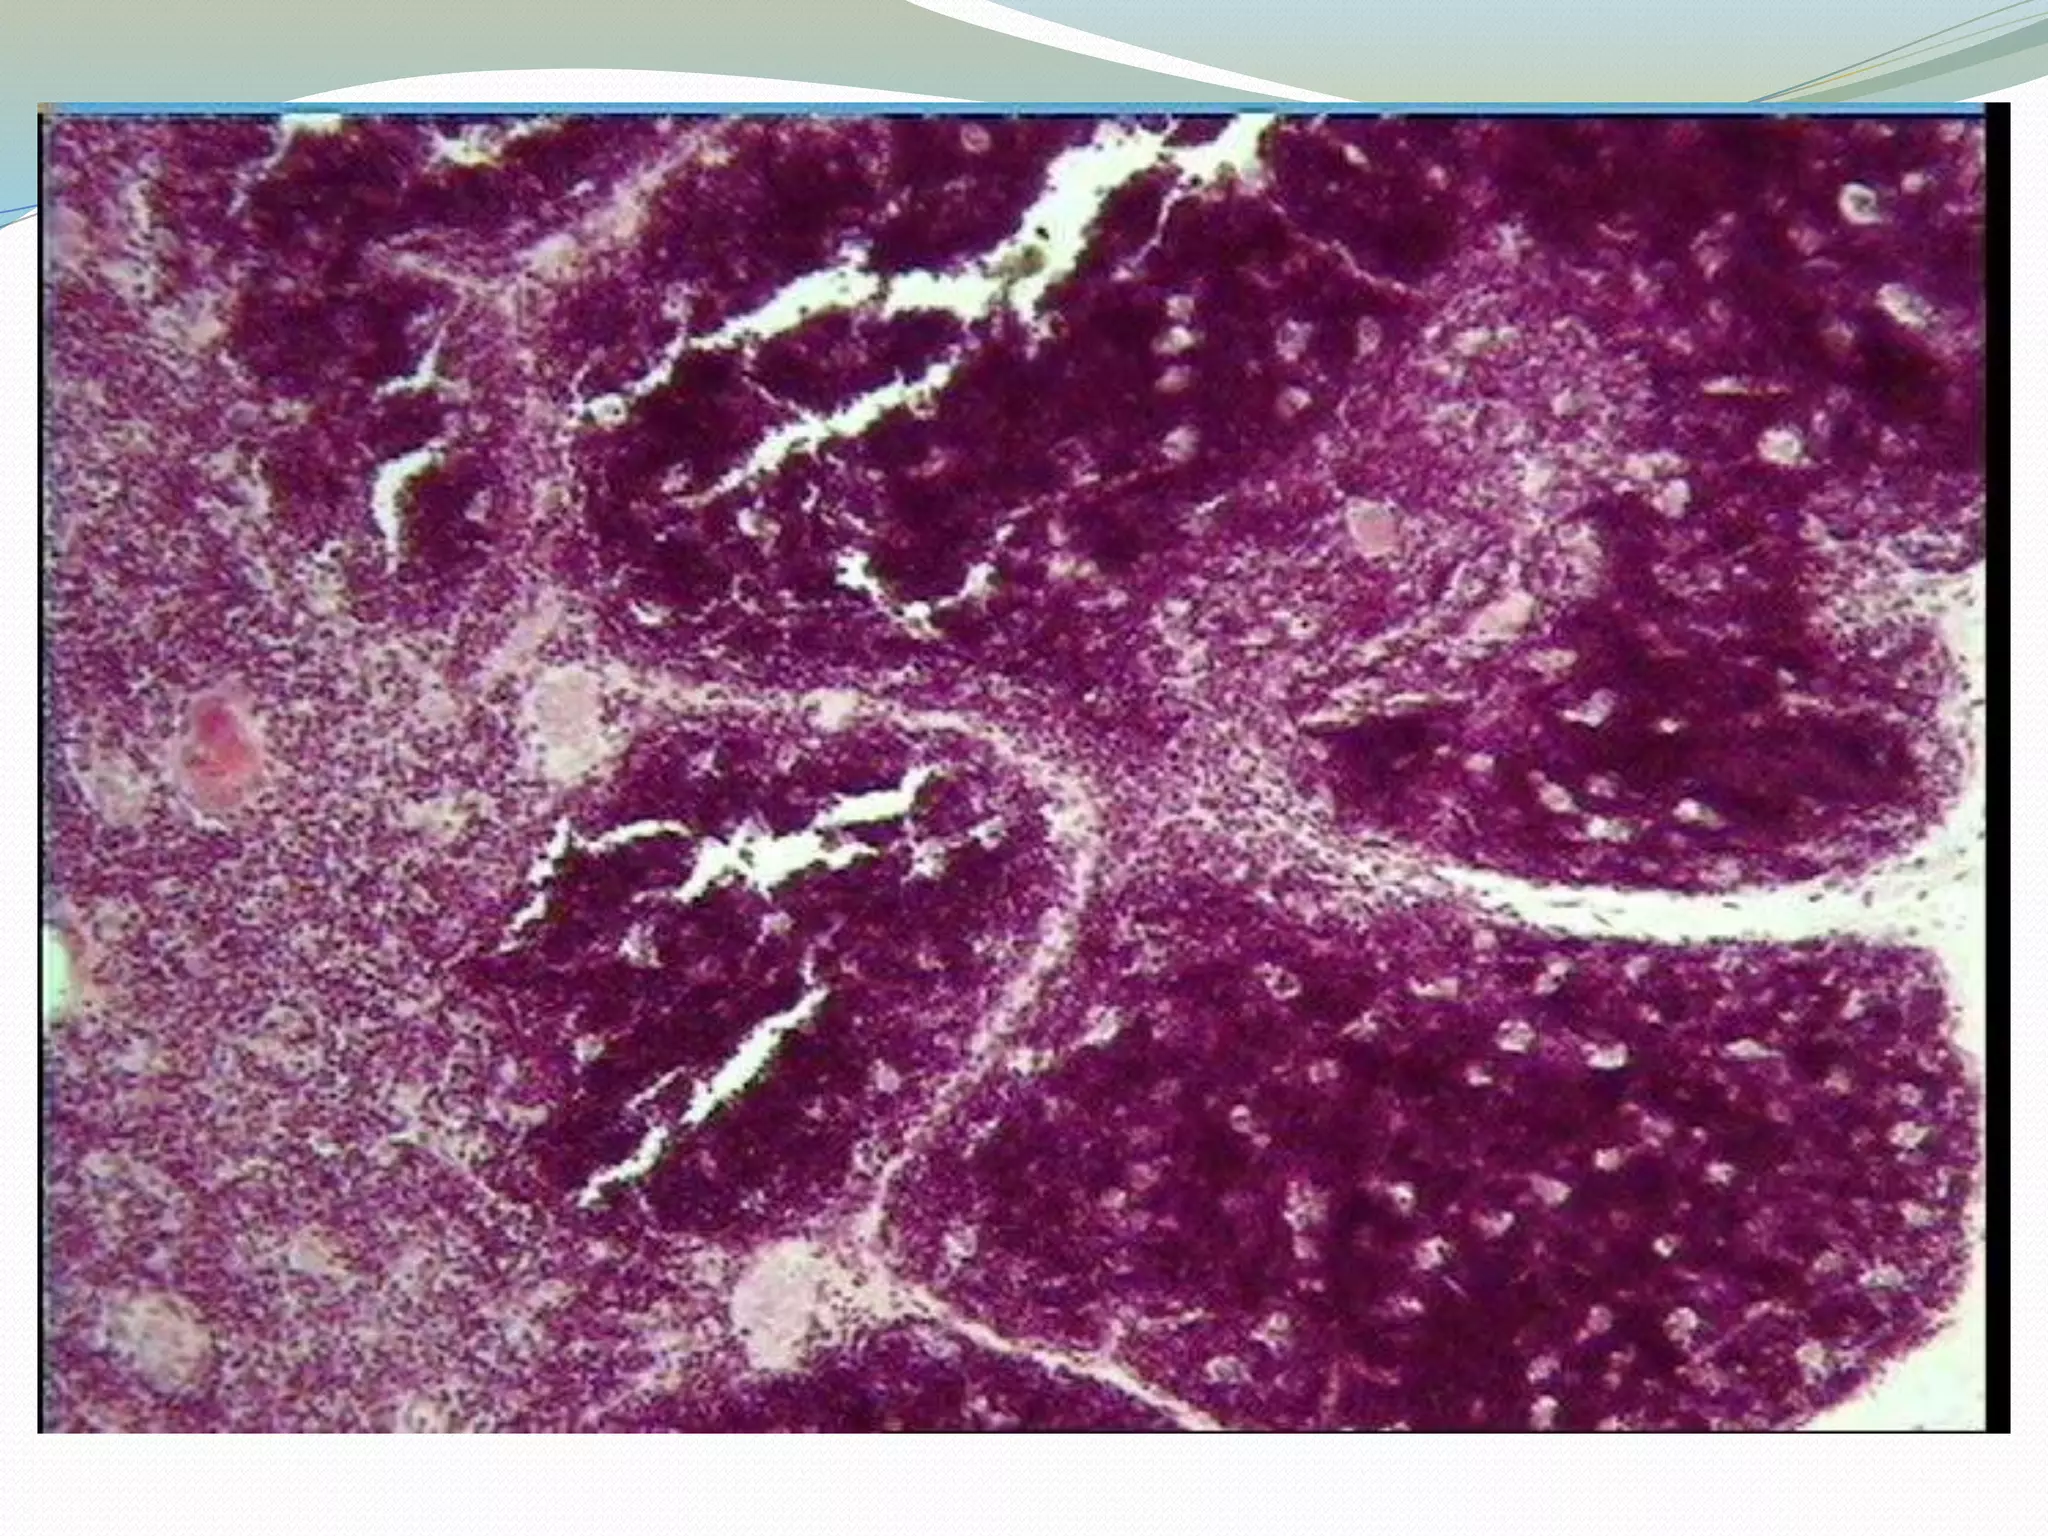

The thymus is enclosed by a

thin connective tissue capsule

from which numerous septa

extend into the thymus

subdividing the two lobes into

numerous lobules (about 0.5 -

2 mm in diameter).

Blood vessels enter and leave

the thymus via the connective

tissue septa.

Each lobulus is divided into a

darker peripheral zone, the

cortex, and a lighter, central

zone, the medulla.

Medullary tissue is

continuous from lobule to

lobule throughout each lobe.

Thymus: Cortex+ Medulla